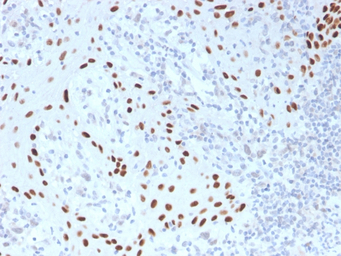

IHC-P analysis of human skin tissue section using GTX02728 p63 antibody [TP40/3980R].